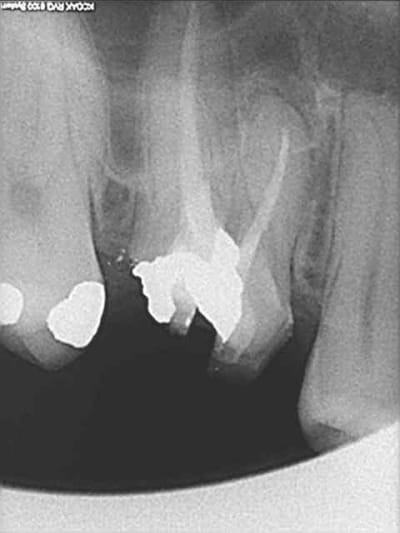

quasiment 6 mois entre les deux interventions (sinus lift et mise à jour)

c'est surtout la qualité des trabéculations osseuses qui m'interpelle.

d'habitude, on voit toujours un peu de particules, ici, c'est vraiment top.

Je suis en tout point d'accord avec toi : ce qui est vraiment intéressant, ce sont les trabéculations osseuses obtenues après cicatrisation.

je crois que c'est la première fois que je vois une cliché radio à quelques mois post-op avec ce matériau et le résultat semble excellent.